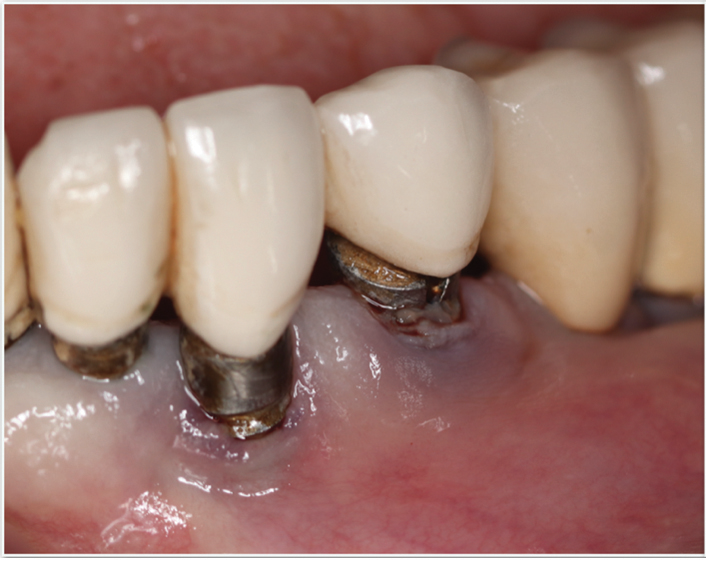

Fig 3 and Fig 4. Pre- (Fig 3) and post-treatment (Fig 4) photographs of a patient who received free gingival grafting at implant sites Nos. 21 and 22. Note the increased amount of keratinized tissue at the areas postoperatively (Fig 4). The patient was placed on 3-month supportive peri-implant care post-surgery and reported increased comfort during her home care regimen.

Figure 3

Tissue thickness has been shown to affect the initial crestal bone loss around dental implants.33 Linkevicius et al demonstrated that thick phenotypes had less initial crestal bone loss than thin phenotypes.33 However, when thin tissues were augmented with human soft tissues (allografts), the crestal bone loss was comparable to thick tissues.33 Therefore, a thicker phenotype is more desirable when evaluating soft-tissue quality around dental implants, and this aspect should be evaluated during maintenance visits. Additionally, the amount of keratinized tissue may affect the long-term prognosis of dental implants. In natural dentition, at least 2 mm of keratinized tissue reportedly is necessary to maintain health of the periodontal tissues.34,35 For dental implants, however, the significance of keratinized tissue in preserving implant health has been less clear, with some early studies showing no association between the amount of keratinized tissue and bone loss and some studies reporting that the presence of keratinized tissue significantly decreases the amount of recession and clinical attachment loss.34-36 Additional studies support a band of keratinized tissue of more than 2 mm to be associated with decreased BOP, plaque, mucosal recession, and attachment loss,34,37 especially when patients are not on a strict maintenance protocol.38 This may be because keratinized tissue provides increased comfort for the patient during home care regimens, whereas pain with brushing and therefore a reluctance to upkeep maintenance may occur with thin peri-implant mucosa (Figure 2).39 As a result, during supportive peri-implant therapy, adequate evaluation of soft-tissue quality around dental implants is crucial, with recommendations for soft-tissue augmentation if needed (Figure 3 and Figure 4).